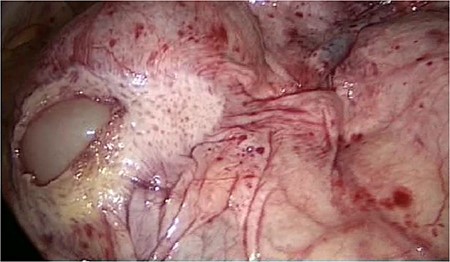

The entire small bowel was found retroperitoneal covered by a slim peritoneal layer (Fig. 1). The dorsal peritoneum covering the ileum was opened (Fig. 2).

We accidentally opened the dorsal peritoneum (Fig. 2), and found the small bowel underneath - retroperitoneal (Fig. 3).